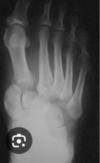

Fx de Jones Base del 5to metacarpiano

Que es la fractura de lisfranc?

Fx Luxación de Art. tarso metatarsiana